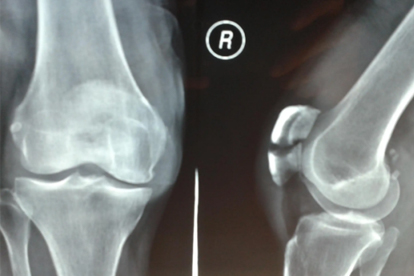

骨折临床愈合后开始部分负重行走,初期使用拐杖分担30%体重负荷,通过步态训练纠正跛行。逐渐增加负重比例至完全弃拐,过程中需定期复查X线确认骨痂形成情况。行走时保持膝关节中立位,避免突然扭转动作。